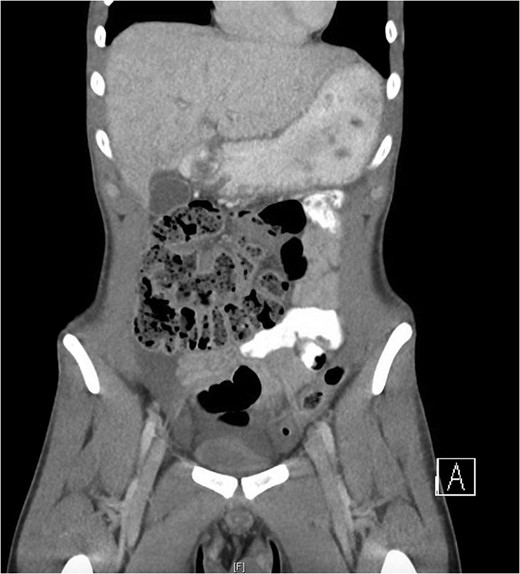

The only notable clinical finding was tenderness in the supra-pubic region. There was no evidence of peritonism. Routine blood tests were normal. Abdomino-pelvic computed tomography (Fig. 1) demonstrated a moderate amount of free fluid on the right side of the abdominal cavity and appendiceal thickening. A testicular ultrasound yielded no significant abnormality. Due largely to the unexplained CT findings, the patient was consented for a diagnostic laparoscopy.